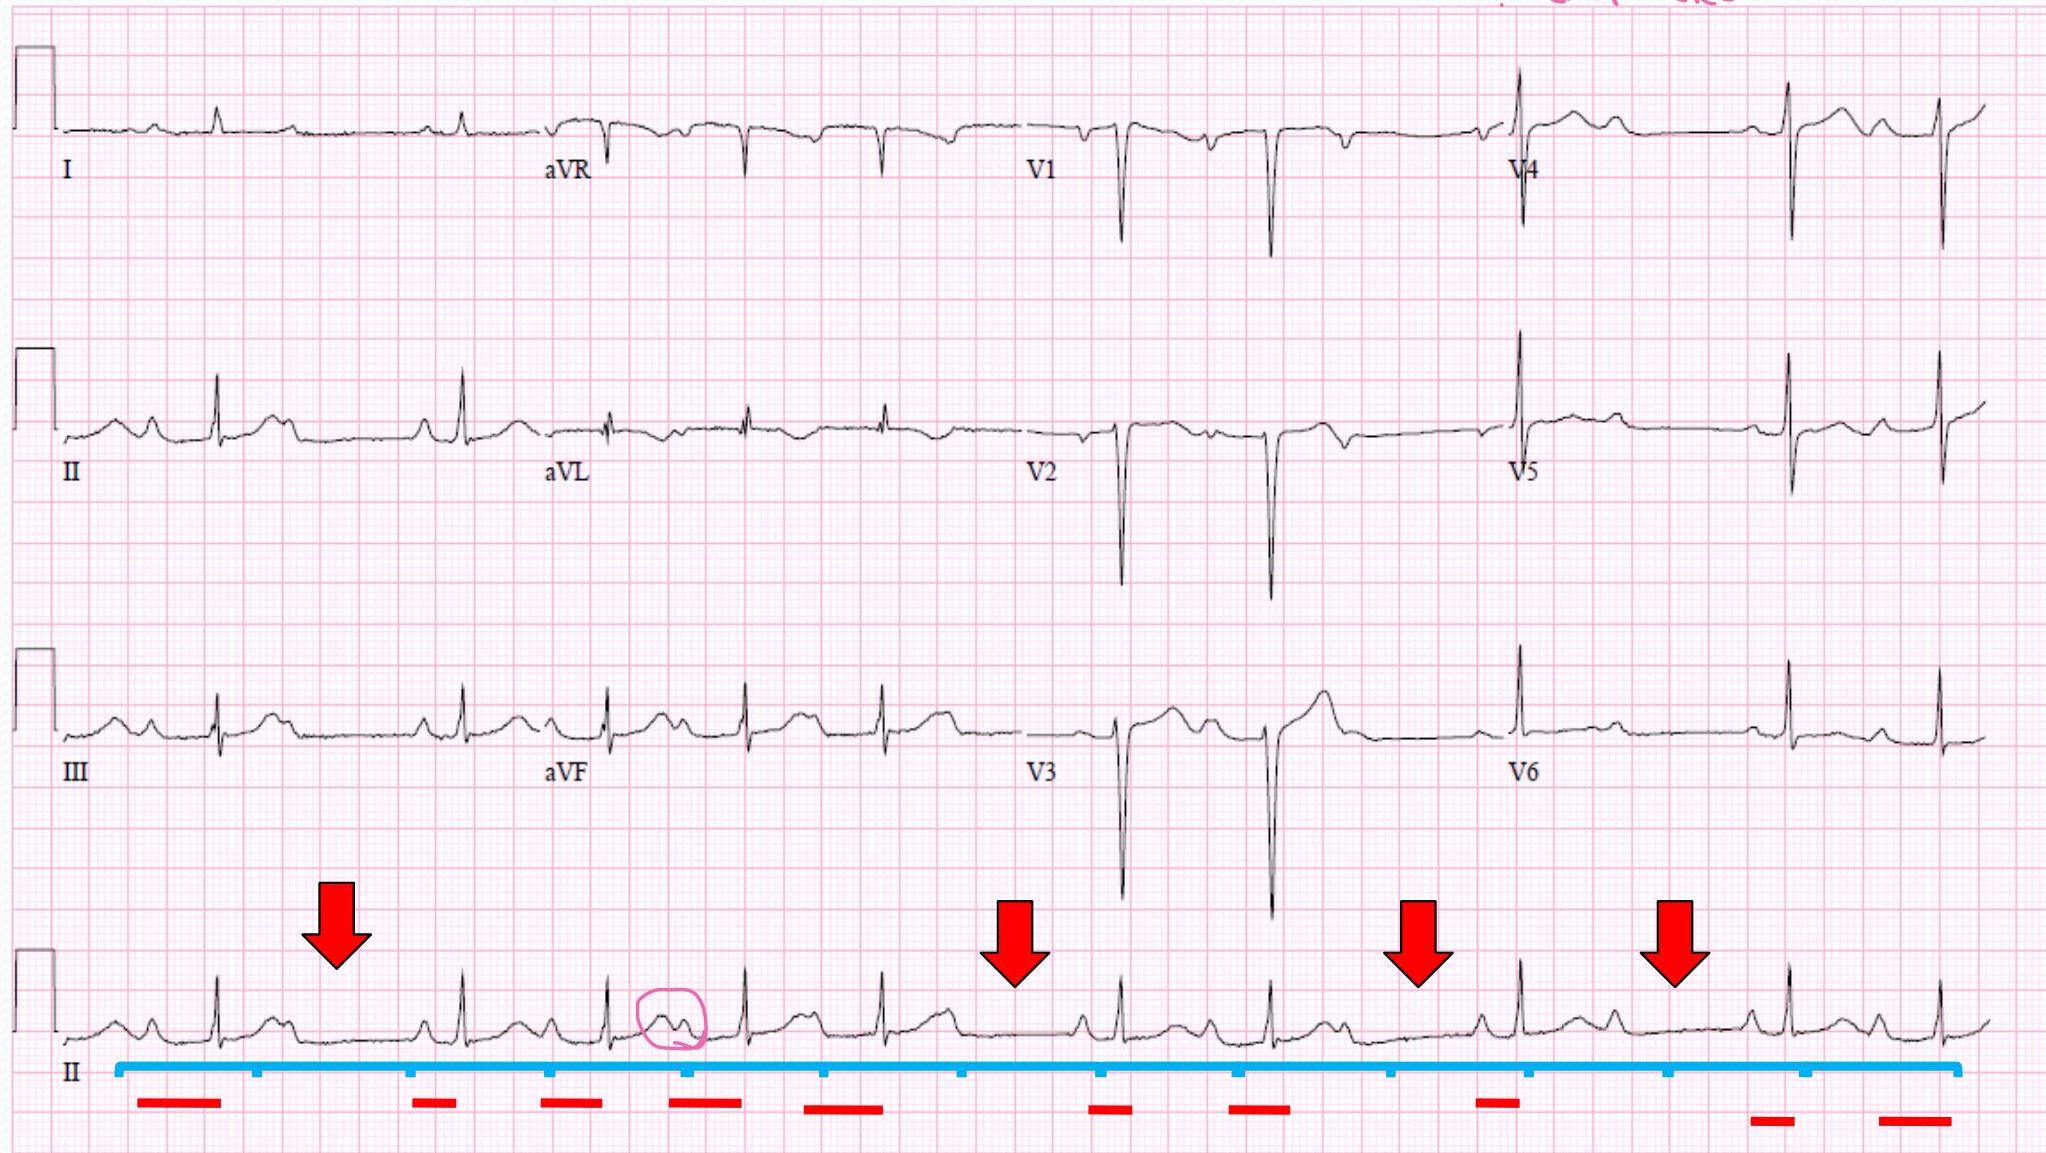

Third Degree AV Block (Complete Heart Block)

- could be with other causes but it’s one of the features of complete heart block

- “Atrioventricular dissociation” no relation between P wave and QRS

- Bradycardia

- Atrial rate more than ventricular rate

- QRS could be wide or narrow (from ventricle itself, just below AV nodes)

| P Wave | PR Interval (in seconds) | QRS (in seconds) | Characteristics |

|---|---|---|---|

| Normal but not related to QRS | None | N/A | No relationship between P&RS |